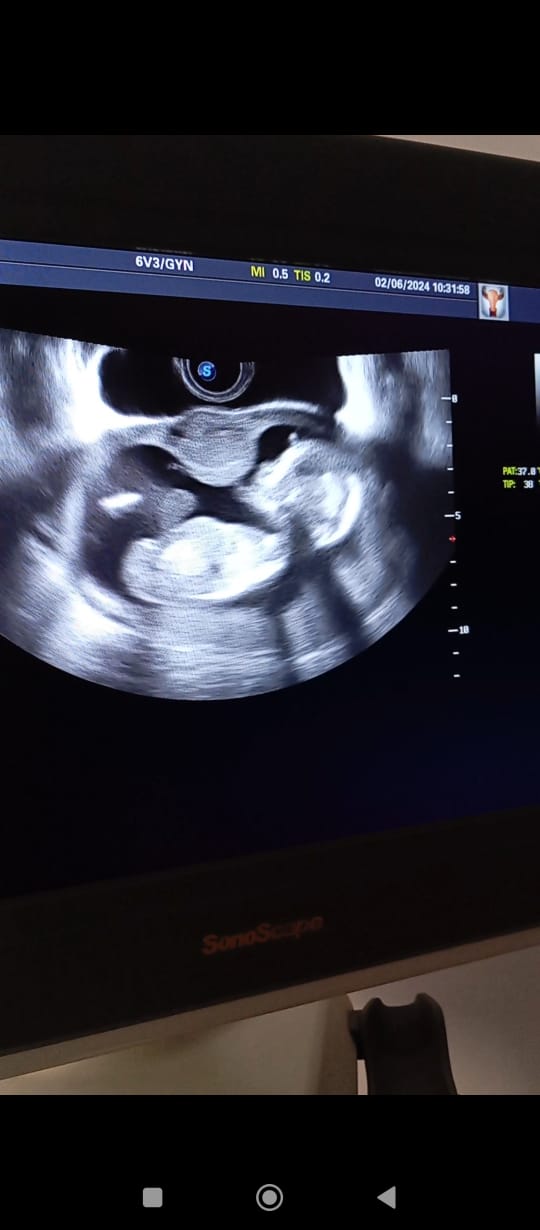

| 10 | Алынган материалдар негизинде макала жазуу жана редактирлоо. PRISCA скрининг тестин колдонуу менен Trisomy 21 коркунучун баалоо боюнча изилдөө жүргүзүү | PRISCA скрининг тестин колдонуу менен кош бойлуулуктун I триместрде (11–14 жума) 50 кош бойлуу аялда Trisomy 21 коркунучун баалоо боюнча изилдөө жүргүзүлдү; изилдөө 2024-жылдын февраль–апрель айларында Ош шаарындагы аялдар консультациясы жана клиникалык лабораторияларда өткөрүлдү; PAPP-A жана free β-hCG көрсөткүчтөрү, УЗИ маалыматтары жана PRISCA алгоритми колдонулуп, статистикалык талдоо жүргүзүлдү; жыйынтыгында Trisomy 21 коркунучунун жогорку, орточо жана төмөн деңгээлдери аныкталып, алынган маалыматтар I триместр скринингинин эффективдүүлүгүн тастыктады. | 2025-05-10 2025-09-01 |

| 3 | Түйүлдүктүн аномалияларына таасир эткен факторлорду талдоо: Биохимиялык жана ультраүндүк скринингдердин негизинде түйүлдүктүн аномалияларына таасир эткен факторлор толук анализденди. | Түйүлдүктүн аномалияларына таасир этүүчү факторлор биохимиялык жана ультраүндүк скринингдердин негизинде терең анализденди. | 2024-10-31 |